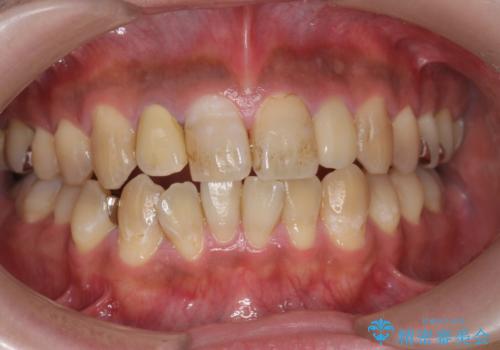

PMTCでコーヒーによる着色を除去。

- コーヒーを毎日飲むため、歯の表面についた着色をとりたいと来院されました。

歯の着色だけでなく、汚れもとれ歯の表面がツルツルになったと

喜んでいただけました。